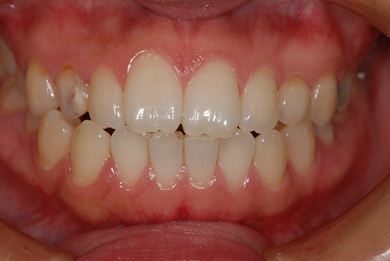

治療前

• 治療前